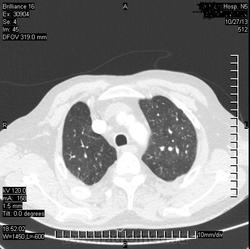

Коллега, а что, инфаркт искали? Или у Вас так окклюзии ЛА ищут? Интересно, а просто ОГК , для искл. пневмонии

( или инфаркт-пневмонии) слева?

Виноват. Не все вчера успел выложить.ТЭЛА.

ТЭЛА слева, я правильно вижу?

Да. Слева.